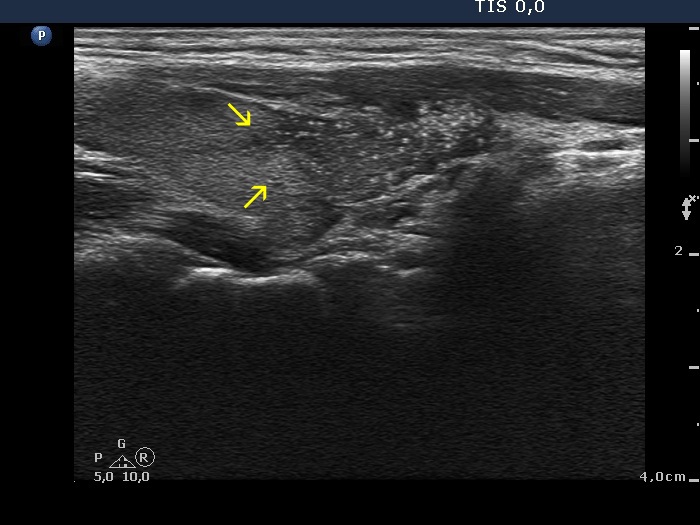

Papillary carcinoma (histology) - case conp005

Transverse scan

Longitudinal scan

The main body of the tumor is pointed with red arrows, while yellow arrows point to infiltration of the parenchyma. The hallmark of these areas is the presence of microcalcifications.